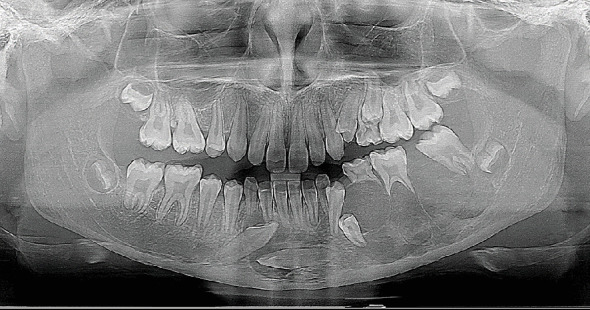

骨肉瘤是最常见的原发性骨恶性肿瘤,很少影响颌骨,仅占病例的6%-10%。颌骨骨肉瘤通常发生在30至50岁之间的个体中,在儿童中并不常见。它通常累及下颌骨,尤其是男性,表现为肿胀、牙齿活动和感觉异常,而不是疼痛。我们提出一个罕见的颌骨骨肉瘤病例在一个12岁的女孩谁表现出感觉异常和显著下颌骨肿块。影像学显示广泛的下颌骨累及Codman三角区,活检证实了常规骨肉瘤的诊断。治疗方法包括半下颌管切除术,随后使用钛板和橡胶垫片进行临时重建。本病例强调了综合评估和多学科管理在儿童颌骨骨肉瘤诊断和治疗中的重要性。对12例类似病例的回顾强调了表现和治疗结果的可变性,强调了个性化治疗计划以优化患者预后的必要性。

Osteosarcoma, the most common primary bone malignancy, rarely affects the jaw, representing only 6%-10% of cases. Jaw osteosarcoma typically occurs in individuals between the ages of 30 and 50 years and is uncommon in children. It often involves the mandible, especially in males, presenting with swelling, tooth mobility, and paraesthesia rather than pain. We present a rare case of jaw osteosarcoma in a 12-year-old girl who exhibited paraesthesia and a significant mandibular mass. Imaging demonstrated extensive mandibular involvement with Codman's triangle formation, and a biopsy confirmed the diagnosis of conventional osteosarcoma. The treatment approach included a hemimandibulectomy, followed by temporary reconstruction using a titanium plate and silastic spacer. This case underscores the importance of comprehensive evaluation and multidisciplinary management in diagnosing and treating osteosarcoma of the jaws in children. A review of 12 similar cases highlights the variability in presentation and treatment outcomes, emphasizing the need for individualized treatment plans to optimize patient prognosis.